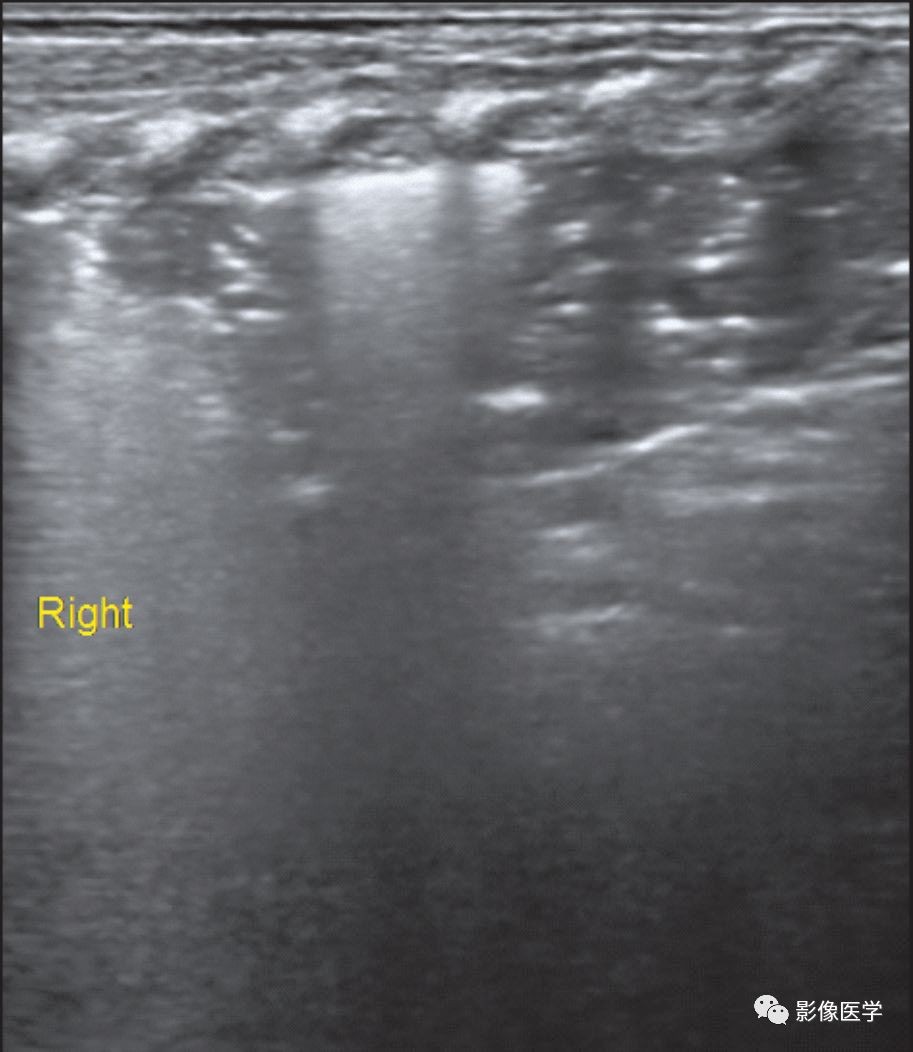

图6-15 社区获得性肺炎(2)

G2P2,胎龄28周。因呼吸困难伴腹泻1d入院。查体:反应差,呼吸困难,三凹征(+),休克状态。双肺均闻及细湿啰音,右肺显著。给予呼吸机治疗。肺脏超声:右肺可见大面积实变伴支气管充气征、边界不规则;左肺以水肿为主要表现,可见累及不到1个肋间的局限性胸膜下小范围实变区(箭头),证实为肺炎。该患儿血培养为肺炎克雷伯菌生长,可能为该患儿感染的病原菌。